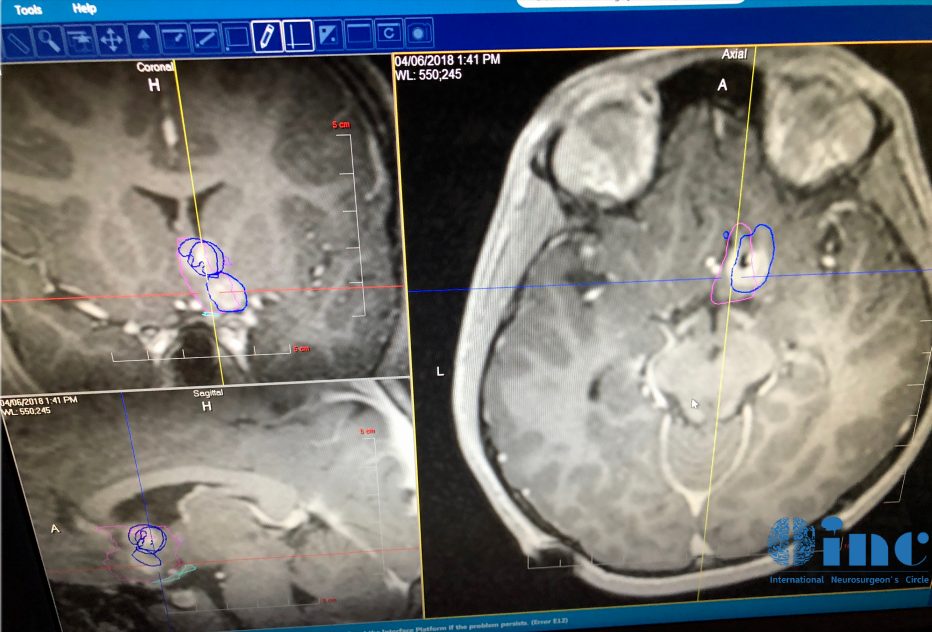

治療過程:一家人找到國際兒童腦瘤教授INC Rutka教授,Rutka教授與Jimmy及其家屬進行了深入溝通,教授認(rèn)為Jimmy的殘余腫瘤不足3cm,適合采用一項微創(chuàng)技術(shù)——激光間質(zhì)熱療(LITT)來消融病變。教授表示術(shù)后Jimmy可以很快出院,不會影響正常的學(xué)習(xí)和生活,與Jimmy一家達成共識后,教授立即為其制定了周詳?shù)奈?chuàng)治療方案。由于Rutka教授團隊對于整個LITT技術(shù)已經(jīng)有豐富的經(jīng)驗,Jimmy的手術(shù)很成功。

治療過程:在MRI引導(dǎo)技術(shù),教授團隊清晰地識別腫瘤與周圍健康腦組織的位置關(guān)系,進而制定精確的手術(shù)路徑,成功消融了Jason腦內(nèi)殘余的病變組織。